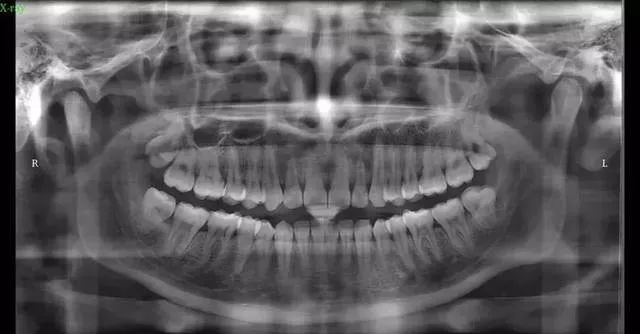

初步沟通后,拍口腔全景片,头颅侧位片、CT等,拍片的目的是为了看你的牙齿及骨骼发展方向等,以利于以后制定准确的矫正方法。